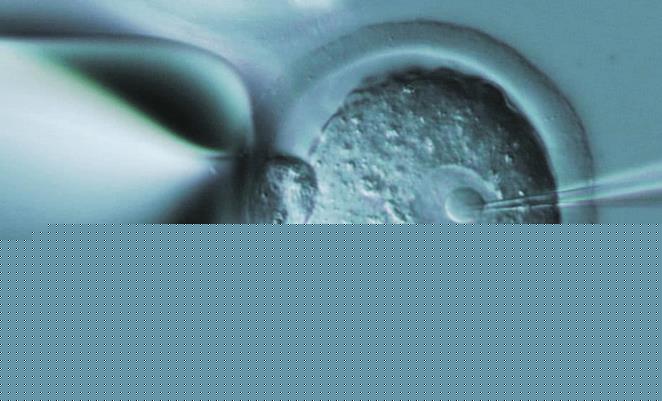

試管嬰兒手術成功率對于每一個患者而言都是非常重要的,患者在做這項手術的時候肯定也在思考,同樣都是做手術,為什么不選擇一個成功率相對較高的醫院,畢竟這對患者本身來講會帶來更多保障。山東臨沂做試管嬰兒成功率最高的醫院是哪里?這也是每一個患者希望能夠提前了解的,當我們在選擇試管嬰兒這項手術的時候,一定要具體情況具體分析,只有這樣才能給我們帶來一系列體驗。

很多患者在選擇試管嬰兒這項手術的時候,會通過各個不同的情況來做多方面了解,一般來說當我們要做試管嬰兒這項手術的時候,可能會考慮到成功率方方面面的因素,其實從目前的情況來看,成功率相對較高的醫院非常多,如果要選擇正規三甲醫院的話,這里的很多三甲醫院都可以給我們帶來更高的成功率,就像是臨沂人民醫院或者是臨沂市婦幼醫院,但是如果我們要選擇私立醫院的話,那么同樣也可以給我們帶來較高成功率。

患者在臨沂地區選擇試管嬰兒醫院的時候,建議患者最好能夠綜合考察,并不是說成功率較高的醫院就一定適合患者,每一位患者在做試管嬰兒之前肯定就會到醫院做檢查,在做檢查的時候,最起碼能夠了解到自己的身體狀況,會了解到自己究竟是什么原因所導致的不孕不育,比如如果是因為女性原因導致的不孕不育,那么我們在選擇試管嬰兒醫院的時候,就要選擇這方面案例相似的情況,這樣才能給我們帶來諸多保障。

簡單的來講,就是患者在選擇試管嬰兒醫院的時候,最好能夠結合自身的實際情況來選擇,而并不是通過其他的方式做選擇,有的醫院可能成功率看起來相對較高,但是可能和我們的癥狀并不相匹配,這種情況下就會對自身產生影響,因此建議患者在選擇試管嬰兒醫院的時候,一定要綜合各個不同的情況來做做考究。